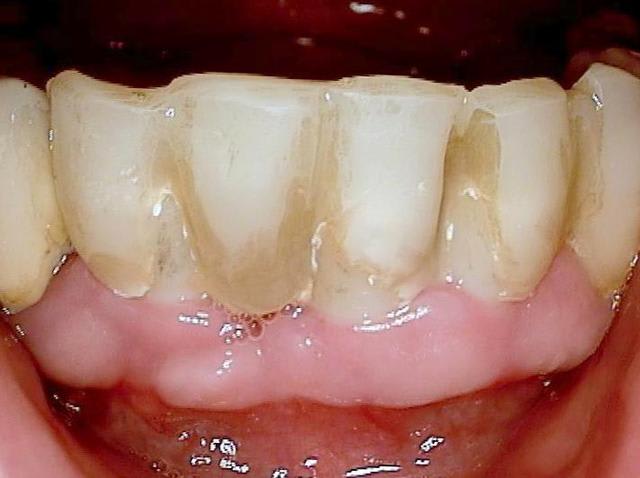

J'ai regardé toutes ces réhabilitations. Le truc qui me chiffonne dans tout ça (sur lequel je m'interroge, pour parler en français académique), c'est la façon dont on assure l'hygiène, avec des embrasures aussi petites et des prothèses qui semble bien proches de la gencive.

En bref : comment ça se nettoie ?

c est une bonne question (merci de m avoir expliquer le sens de chiffonne :-) l expression est marrante)

une bonne hygiène est surtout importante si le patient est malade par exemple suite à un "schlaganfall" (en allemand je ne sais pas le terme en francais)

les "vieux" systèmes deux pièces ont un micro espace de 30 micromètres , ce qui explique que les patients devaient nettoyer péniblement ...

en ceramique il n y a pas d accumulation de plaque donc pas de grandes concentration de bactéries gram negatif et anaerobie.La gencive se forme très bien autour de la ceramique ( la nature est le meilleur architecte!)

si après quelques années les couronnes sont retirées, on voit pas d infection....

pour finir c est sur qu il faut quand même se brosser les dents régulièrement. Les patients reviennent juste deux fois par an pour un nettoyage professionnel...

Oui tu as bien raison :-) Ci joint quelques photos en rapport avec ta question ....